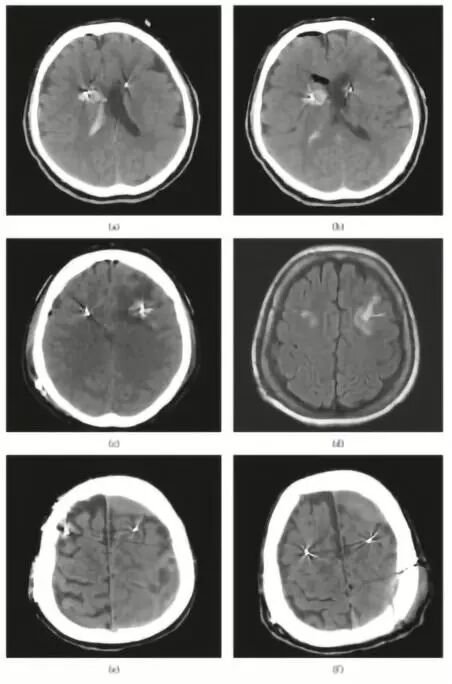

近期并发症主要有,6.6%患者意识混乱或精神状态改变、2.2%脑出血、1.1%脑缺血性卒中和1.1%癫痫发作。远期并发症有,7.2%患者伤口感染和5.5%出现与硬件相关的不良事故。其它并发症包括慢性硬脑膜下血肿,占1.1%(图1)。

图1. DBS术后CT扫描显示并发症。a、b.右侧尾状核血肿伴右侧脑室内出血;c.左额电极周围静脉性梗死灶;d.6个月后CT复查,病灶消失;e.左侧额、顶叶慢性硬膜下血肿;f.为避免电极移位,清除左顶血肿后,左额血肿未处理。